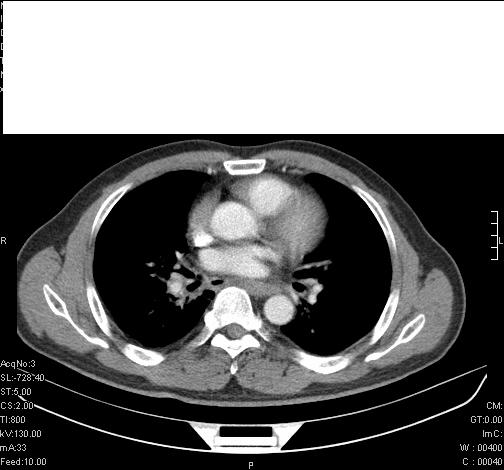

前几天,发了患者的平扫片,患者抗炎一周后增强扫描。右中叶病灶吸收明显,但下叶病灶未见明显吸收。右肺门可见结节影,看来凶多吉少

右肺下叶支气管壁明显增厚,考虑癌症并阻塞性炎症、肺门淋巴结肿大

考虑右肺癌并阻塞性炎症、肺门淋巴结肿大

还是考虑右肺中央型肺癌可能性大

考虑右肺中央型肺癌可能性大

右主支气管狭窄,管壁增厚。考虑右中心性肺ca伴阻塞性肺炎。